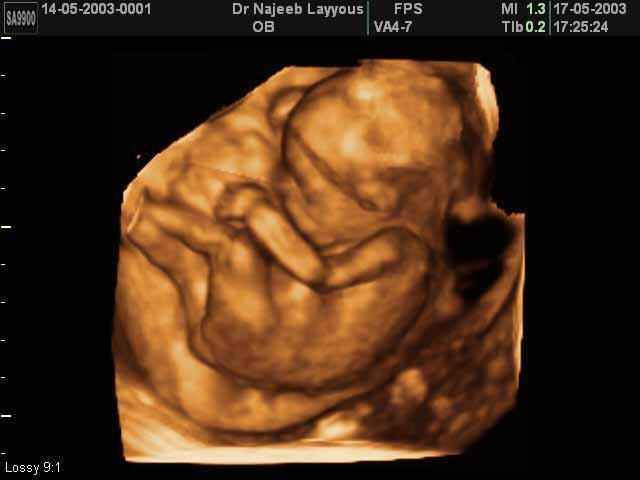

- Fetal Behavior Ultrasound Photos

3D Second Trimester Ultrasound Scan Photos-second part of pregnancy | Dr N Layyous